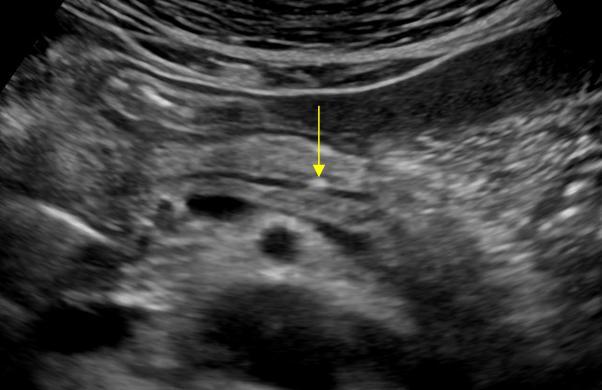

УЗИ диагностика кольцевидной поджелудочной железы: что важно знать